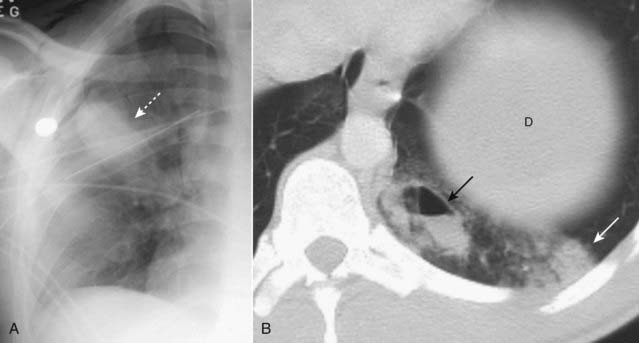

image

Figure 17-1 Rib fractures.

Rib fractures are important primarily for the complications they might produce or the unsuspected pathology they might herald. Fractures of the first three ribs (solid white arrows) are relatively uncommon; following blunt trauma, their presence is a clue that the force to the chest may have been sufficient to produce other internal injuries. Don’t mistake the normal costovertebral junction (solid black arrow) for a fracture.

Figure 17-2 Flail chest.

There are two or more fractures (dotted white arrow demonstrates second fracture in rib 4) present in more than three contiguous ribs (solid white arrows). The airspace disease in the left lung is an underlying pulmonary contusion, which almost always accompanies a flail chest.